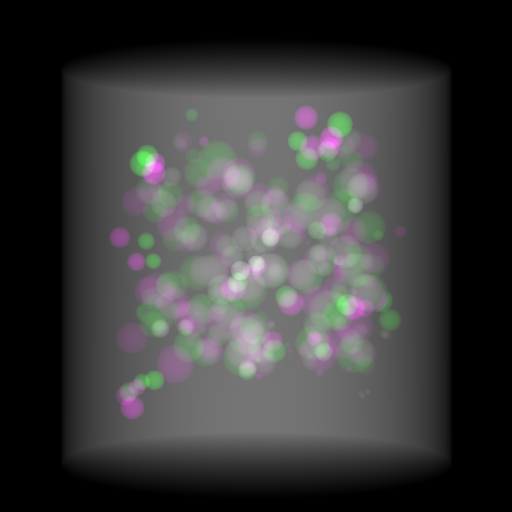

Figure 5: Perspective projection images from two orthogonal views for a 3D bead phantom as an example: (a) a 3D bead phantom where the background cylinder is omitted for better visualization of the beads; (b) the perspective projection of the 3D bead phantom from the 0superscript00^{\circ} view; (c) the perspective projection of the 3D bead phantom from the 90superscript9090^{\circ} view; (d) the RGB stack of the 0superscript00^{\circ} and 90superscript9090^{\circ} perspective projection images; (e) the RGB stack of the 0superscript00^{\circ} and 90superscript9090^{\circ} OPBP images. The intensity range [0, 11] in projection images is converted to [0, 255] for visualization.

As an illustrative example, the two perspective projection images from two orthogonal views for a 3D bead phantom are displayed in Fig. 5. To better compare the perspective projection images from the two orthogonal views, an RGB image is formed in Fig. 5(d), where the red and blue channels use images from the 0superscript00^{\circ} perspective view, while the green channel uses images from the 90superscript9090^{\circ} perspective view. Here we fill up three channels so that pixels, which have similar intensity from both views, appear grey such as the background cylinder area. In the formed RGB image, the magenta beads from the 0superscript00^{\circ} view and the green beads from 90superscript9090^{\circ} view are located in different positions. Similarly, an RGB image consisting of the 0superscript00^{\circ} perspective projection image (red and blue channels) and the 90superscript9090^{\circ} OPBP image (green channel) is displayed in Fig. 5(e). In Fig. 5(d) the bead-to-bead (or point-to-point) correspondence between two views is not straightforward because of the large number of beads. It is the same for the bead-to-stripe (point-to-line) correspondence in Fig. 5(e). Therefore, it is challenging for neural networks to learn perspective deformation from two orthogonal views.